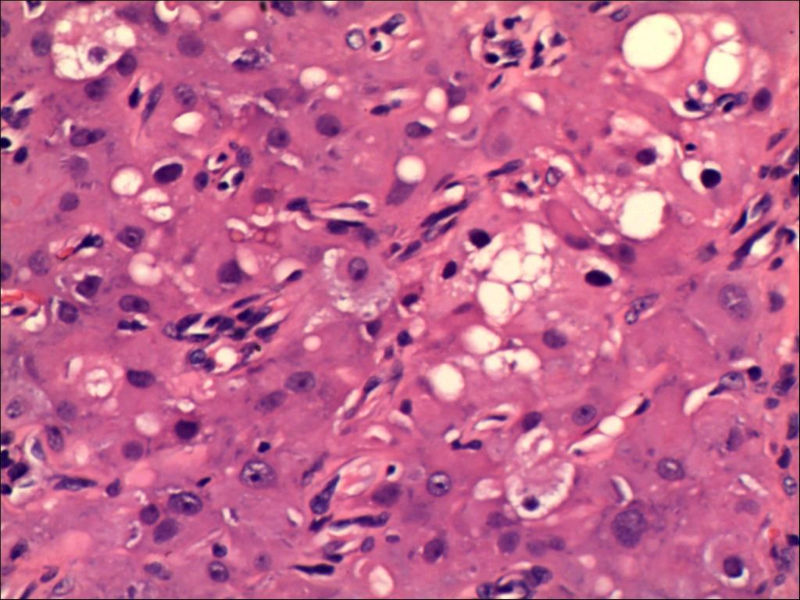

女,27岁,送检右侧卵巢肿物(另外还送检左侧卵巢肿物,大体及镜下显示为畸胎瘤),卵圆形,大小2×1×1cm,似有包膜。卵巢肿物图1

卵巢畸胎瘤中正常卵巢的黄体组织,铺砖样排列,胞浆宽大,较典型。

不好意思,可能是我没说清楚,患者对侧卵巢是畸胎瘤,不是同一侧的,我初步考虑门细胞瘤,图21,22,24,25,26中央的一些细胞是不是很像门细胞

谢谢大家的回答和解疑,忘记一个重要的病史,就是该女性为产妇。但是妊娠黄体瘤与类固醇细胞瘤怎么鉴别呢

那应该是妊娠黄体/黄体瘤,类固醇细胞瘤有嗜酸细胞和组织细胞样细胞两种,此例显然不是。